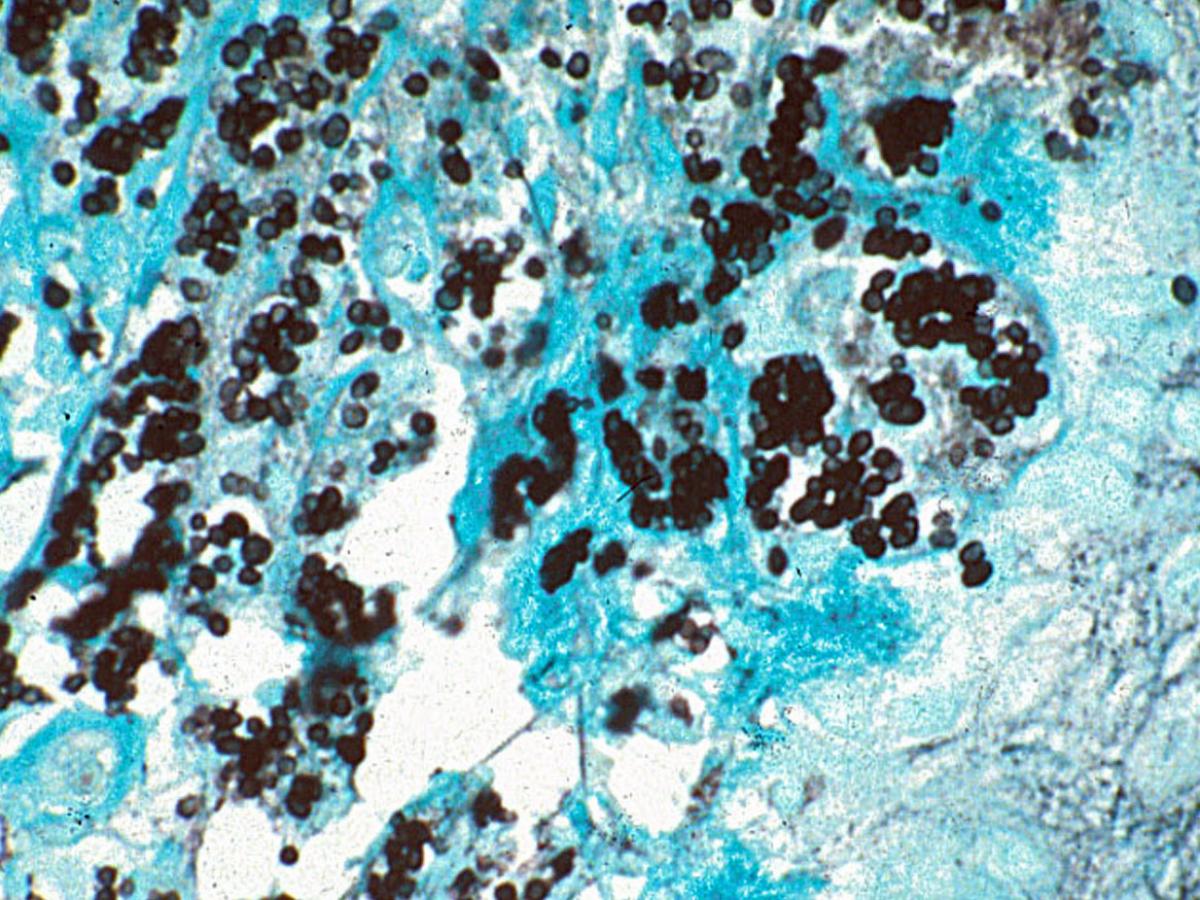

Direct microscopy (GMS staining): The yeast-cells are spherical to ellipsoidal, 2 to 6 um in diameter, and divide by fission rather than budding, a characteristic visible on stained touch smears that distinguishes T. marneffei from Histoplasma capsulatum.

A Giemsa stained touch smear of a skin biopsy or bone marrow aspirate is a rapid and sensitive diagnostic method that readily demonstrates the presence of typical yeast-like cells with a central septa, either within histiocytes or scattered through the tissue.